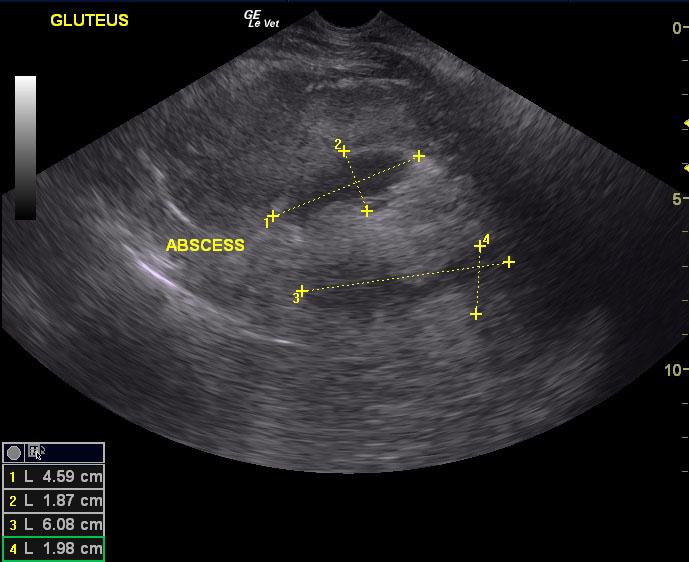

A 7-year-old MN Labrador Retriever was presented for severe hind limb swelling, bruising in the inguinal region (Image 1) and grade 3 limp. Mild fever was present. Radiographs revealed severe soft tissue swelling of around the femur without bone involvement. Thoracic and abdominal radiographs were unremarkable.

A 7-year-old MN Labrador Retriever was presented for severe hind limb swelling, bruising in the inguinal region (Image 1) and grade 3 limp. Mild fever was present. Radiographs revealed severe soft tissue swelling of around the femur without bone involvement. Thoracic and abdominal radiographs were unremarkable.